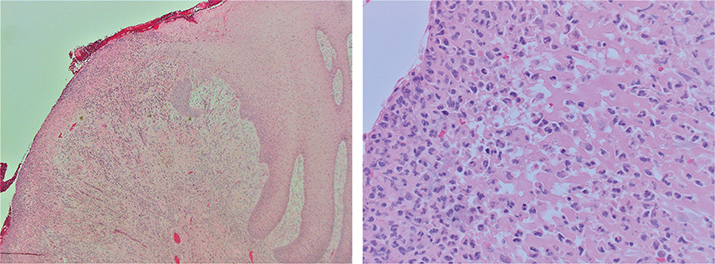

In June 2015, the patient reported increased pain from the enlarged ulcer without improvement of symptoms. A new excision was performed (Figure 2a), where HPE did not show any signs of dysplasia, but revealed an ulceration with fibrinous crusta, inflammation, and extensive infiltrates of neutrophil granulocytes (Figure 2b and c). At a revisit in September 2015, there was an ulcer with fungal infection. Fluconazole was administered, and the patient was called in for re-examination in December 2015. At that point, the lesion had developed an exophytic appearance on the lateral side of the tongue (Figure 3). In February 2016, treatment with radiofrequency ablation of the tongue was carried out (Figure 4). HPE displayed moderately to severely inflamed mucosa, with fibrosis and an ulcer consisting of eosinophil-rich infiltrates with candida infection. There were still no signs of malignancy or dysplasia. Antimycotics were administered.

Fig 2

Figure 2. (a) In June 2015 an increase in size of the ulcer was seen and an excision was performed. (b) & (c) Micrographs showing ulceration with fibrinous crusta and infiltrate of neutrophil granulocytes. Hematoxyline and eosin staining at × 40 (2b) and × 400 (2c).